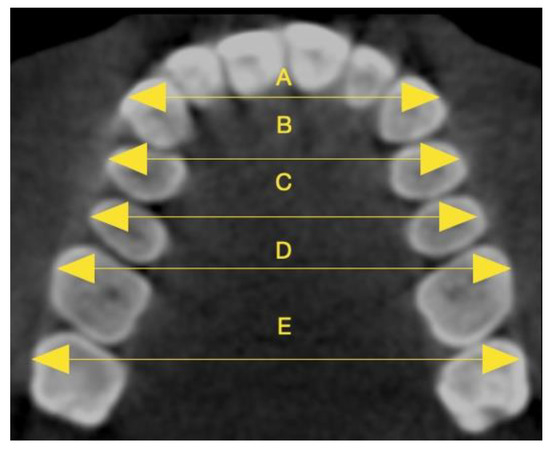

| Inter-Cusp Width | T1-T0 (mm) (Mean ± SD) | T1-T0 Minimum–Maximum Values (mm) | T1-T0 (%) (Mean ± SD) | T1-T0 Minimum–Maximum Values (%) | p-Value |

|---|---|---|---|---|---|

| Intercanine | 2.32 ± 0.33 | 1.40–3.60 | 7.37 ± 1.11 | 4.18–11.76 | 2.39215 × 10−43 ** |

| First interpremolar | 3.44 ± 0.22 | 3.10–3.90 | 8.65 ± 0.60 | 7.71–10.13 | 1.1346 × 10−60 ** |

| Second interpremolar | 3.14 ± 0.27 | 2.70–3.60 | 6.94 ± 0.65 | 5.71–8.13 | 5.72304 × 10−54 ** |

| First intermolar | 2.60 ± 0.52 | 0.40–3.40 | 5.74 ± 1.19 | 0.90–7.64 | 1.4256 × 10−35 ** |

| Second intermolar | 0.70 ± 0.28 | 0.10–1.80 | 1.24 ± 0.51 | 0.18–3.24 | 1.2904 × 10−22 ** |